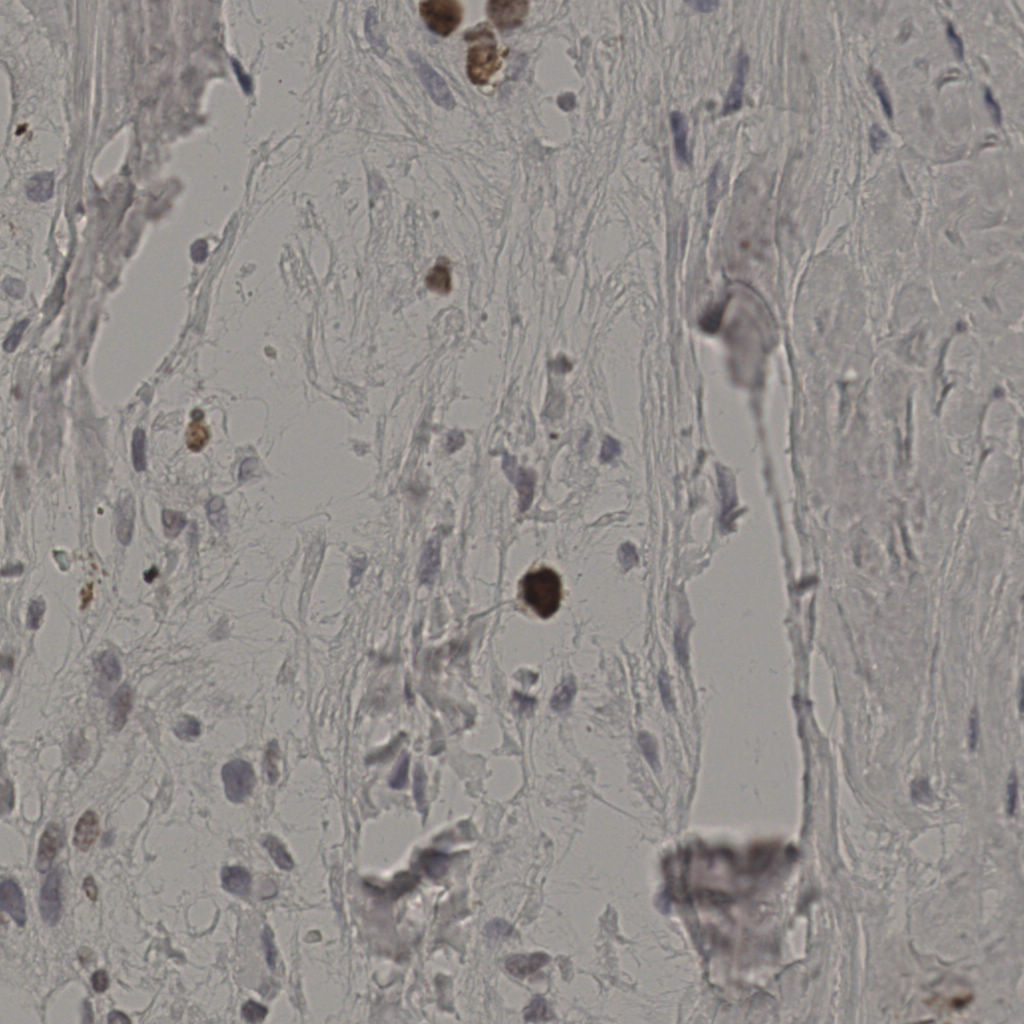

缩略图

标记后

标记前